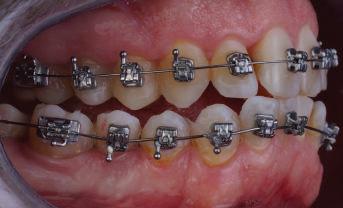

20 Dental Tribune Bulgarian Edition / октомври 2022 г. П ациентите със завършен растеж и скелетни проблеми обикновено представляват предизвикателство за ортодонт ската практика. Необходимостта от изваждане на зъби в комбинация с особеностите на възрастовата ортодонтия изисква особено внима ние. Фокусът върху критично важното значение на позицията на долните резци във връзка с дългосроч ната стабилност и постигането на оптимални оклузални взаимоотношения при затварянето на екстракционните пространства лесно може да излезе извън контрол. Когато към тези чисто кли нични проблеми се добави и стресът от натоваре ната практика, предизвикателството става още по-голямо. Всички тези фактори налагат използ ването на доказан подход с ясни и последовател ни стъпки, в което се разкрива силата на дисциплината „Алекзандър“ – предвидим протокол през целия процес на елиминиране на ротациите, ниве лиране на дъгите, затваряне на екстракционните пространства и финализиране на случая. Именно такъв е и случаят, който презентираме –екстракционен, скелетен клас 3 при възрастен па циент, лекуван по системата „Алекзандър“. ПРЕДВИДИМИ РЕЗУЛТАТИ ПРИ ПАЦИЕНТИ СЪС ЗАВЪРШЕН РАСТЕЖ И СКЕЛЕТЕН КЛАС 3, ИЗПОЛЗВАЙКИ ЕКСТРАКЦИОННО ЛЕЧЕНИЕ ПО ДИСЦИПЛИНАТА „АЛЕКЗАНДЪР“ Д-р Радой Димитров, България Преди започване на лечение клиничен случай | ортодонтия Фиг. 1а–1e Преди започване на лечение. Пациентът пристига в практиката с основното оплакване от невъзмож ност за нормално дъвчене. Снета е цялата необходима диагностична ин формация. Фиг. 1f–1h Снимки в профил и анфас. Фиг. 1i–1k Панорамна снимка, телерентгенография и анализ на телерент генография. Фиг. 1а Фиг. 1d Фиг. 1f Фиг. 1g Фиг. 1h Фиг. 1e Фиг. 1b Фиг. 1c Фиг. 1i Фиг. 1j Фиг. 1k

closed.

21Dental Tribune Bulgarian Edition / октомври 2022 г. ДИАГНОСТИЧНИ РЕЗУЛТАТИ: 1. Възраст на пациента: 21 години 2. Скелетен клас III (ANB 0) 3. Зъбен клас 3 4. Ръбцова захапка във фронта, кръстосана в дисталните участъци 5. Тясна горна челюст 6. Overjet – 0 мм, Overbite – 0 мм 7. Несъответствие на горната с долната средна линия 8. Единични контакти в ЦО 9. Хиподивергентен тип на растеж SN/MP – 33.5 10. Неравен гингивален контур 11. Неравна линия на усмивката 12. Тенденция за рецесии в долен фронт ПРЕПОРЪЧИТЕЛНО ЛЕЧЕНИЕ: Пълно ортодонтско лечение с метални брекети „Алекзандър“ Корекция на клас 3 захапката в областта на кучешките зъби с екстракция на първите пре молари в долна челюст Корекция на кръстосаната захапка в дистални участъци Коригиране на ръбцовата захапка във фронта Подобряване на ОJ и OB на пациента Стрипинг в долен фронт Подреждане на зъбите в горната и долната челюст Професионално хигиенизиране и профилактични дентални прегледи са препоръчителни на всеки 6 месеца. 1-ви месец След 1 месец са залепени брекети в горната челюст – поставена е еластична дъга. 016 NiTi. В долната челюст са елиминирани ротациите, поставена е стоманена дъга. 016SS, закалена с ток, и еластична верижка за затваряне на пространствата. 3-ти месец В долната челюст е поставена трета дъга – 17 x 25 NiTi с къси лигатури и верижка

В горната челюст се затварят пространствата с дъга .016SS и верижка. 5-и месец На 5-ия месец след залепяне на брекетите в долната челюст е поставена стоманена дъга 16 x 22 SS с четвъртито сечение, омега луп и тай бек. В горната челюст е поставена дъга 17 x 25 NiTi. Поради липсата на стабилни оклузални контакти са поставени лингвални верижки в областта на моларите, за да се предотврати нежелана ротация на 7-ите зъби. 6-и месец На 6-ия месец от началото на лечението са екстрахирани долните първи премолари, поставена е дъга 16 x 22 SS със затваряща чупка teardrop. Чупката се активира всеки месец по 1 мм с чинч-бек. клиничен случай | ортодонтия СТЪПКИ НА ЛЕЧЕНИЕТО Начало на лечението Лечението започва с поставяне на апарат за бърза експанзия в горната челюст. През първия месец от лечението са направени 24 оборота на апарата за експанзия. Залепени са брекети в долната челюст, поставена е дъга 17x25 CuNiTi, като са предпи сани клас 3 ластици (1/4”,4 1/2 oz) по време на сън, за да се осигури контрол върху торка на долните резци. Фиг. 2а Фиг. 3a Фиг. 4a Фиг. 3b Фиг. 4b Фиг. 3c Фиг. 4c Фиг. 3d Фиг. 4d Фиг. 3e Фиг. 4e Фиг. 5a Фиг. 5b Фиг. 5c Фиг. 5d Фиг. 5e Фиг. 6a Фиг. 6b Фиг. 6c Фиг. 6d Фиг. 6e Фиг. 7a Фиг. 7b Фиг. 7c Фиг. 7d Фиг. 7e Фиг. 2b Фиг. 2c Фиг. 2d

Dental Tribune Bulgarian Edition / октомври 2022 г.22 клиничен случай | ортодонтия 14-и месец В горната и долната челюст са поставени последни стоманени дъга с омега луп и тай бек – 17 x 25 SS с четвъртито сечение. Назначени е ластик за средната линия в комбинация с клас 3 ластик (1/4”, 6 1/2 oz). Контролни рентгенографии 13-и месец Екстракционните пространства са затворени. Направена е контролна панорамна снимка за оценка позицията на корените. Взето е решение за презалепване на брекетите на 12, 22 и пръстените на 36 и 46. 21-ви месец Средната линия в горната и долната челюст съвпадат. Ластиците са спрени. Свалени са пръстените и брекетите в горната и долната челюст, зигзаг ластици не са използвани поради благоприятните оклузални взаимоотношения. Фиг. 11j Ортопантомография в края на лечението. Фиг. 11k Телерентгенография след края на лечението. Фиг. 11l Анализ на телерентгенографията след лечението. Фиг. 11m Последователност на дъгите в горната и долната челюст Фиг. 11n Суперимпозиция на PreOp и PostOp ортопантомографии. 10-и месец Затварянето на пространствата е предвидимо и контролирано, без да се отварят пространства в зъбната дъга. Фиг. 8a Фиг. 8b Фиг. 8c Фиг. 8d Фиг. 8e Фиг. 10a Фиг. 10b Фиг. 10c Фиг. 10d Фиг. 10e Фиг. 9a Фиг. 9b Фиг. 9c Фиг. 9d Фиг. 9e Фиг. 9f Фиг. 11a Фиг. 11f Фиг. 11j Фиг. 11l Фиг. 11m Фиг. 11n Фиг. 11k Фиг. 11g Фиг. 11h Фиг. 11i Фиг. 11b Фиг. 11c Фиг. 11d Фиг. 11e

Dental Tribune Bulgarian Edition / октомври 2022 г. 23клиничен случай | ортодонтия реклама Лечението е продължило 21 месеца. Проведено е домашно избелване с индивидуални шини. За автора: Д-р Радой Димитров завършва с отличие Факултета по дентална медицина към МУ–София през 2015 г. В продължение на 5 години работи в няколко водещи практики в София, като през 2019 г. заедно със своята съпру га д-р Траяна Димитрова основават собствена практика в гр. Гоце Делчев –Dimitrovi Dental Care. Посещава редица курсове за повишаване на квалификаци ята, но най-сериозен тласък в развитието на ортодонтската си практика получава след завършването на комплексната ортодонтска програма, воде на от д-р Иван Горялов, базирана на дисциплината „Алекзандър“ – система с повече от 50 години опит в целия свят. Д-р Димитров е член на Българския изследователски клуб „Алекзандър“. Взе ма участие като гост-лектор в симпозиума с международно участие The Power of the Alexander Discipline, който се проведе на 14–15.05.2022 г. С д-р Ди митров можете да свържете на тел. +359885 252 025. Заключение Представеният случай е ярък пример за възможностите и красо тата на дисциплината „Алекзандър“ – приложен е утвърден под ход с ясни правила и са постигнати очакваните цели. Резулта тът ще бъде дългосрочно стабилен, тъй като са спазени всички правила, които се отнасят към максимално комфортната пози ция на зъбите в края на лечението. Постигнати са красива усмив ка и стабилна оклузия. ПОСТИГНАТИ РЕЗУЛТАТИ ОТ ЛЕЧЕНИЕТО 1. Коригирана ръбцова захапка 2. Коригирана клас 3 захапка в областта на ку чешките зъби 3. Коригирана кръстосана захапка в дисталните участъци 4. Коригиран овърджет и овърбайт 5. Разширена е горната зъбна дъга 6. Подредени зъби в горната и долната челюст 7. Постигната е стабилна захапка с множество контакти в ЦО 8. Драматично е подобрена дъвкателната функ ция 9. Подобрена е линията на усмивката ДРУГИ ПРОВЕДЕНИ ДЕНТАЛНИ ПРОЦЕДУРИ 1. Домашно избелване на зъбите 2. Екстракция на мъдреците Фиг. 12a Фиг. 12b Фиг. 12c Фиг. 12eФиг. 12d Фиг. 12f Фиг. 12g Информация за дати, цени и отстъпки www.bracescourses.com 0889 22 55 01 Практически курсове лектор д-р Иван Горялов Дисциплината „Алекзандър“ ПЪТЯТ КЪМ СУПЕРУСМИВКИТЕ 100% връщане на цялата сума, ако не сте удовлетворени след преминаване на Ниво 1 Директно и индиректно залепяне на брекети Анализ, диагноза и план на лечение Лечение на клас 2 дълбока захапка Екстракционно лечение Лечение на клас 3 отворена захапка НИВО 5НИВО 1 НИВО 2 НИВО 3 НИВО 4